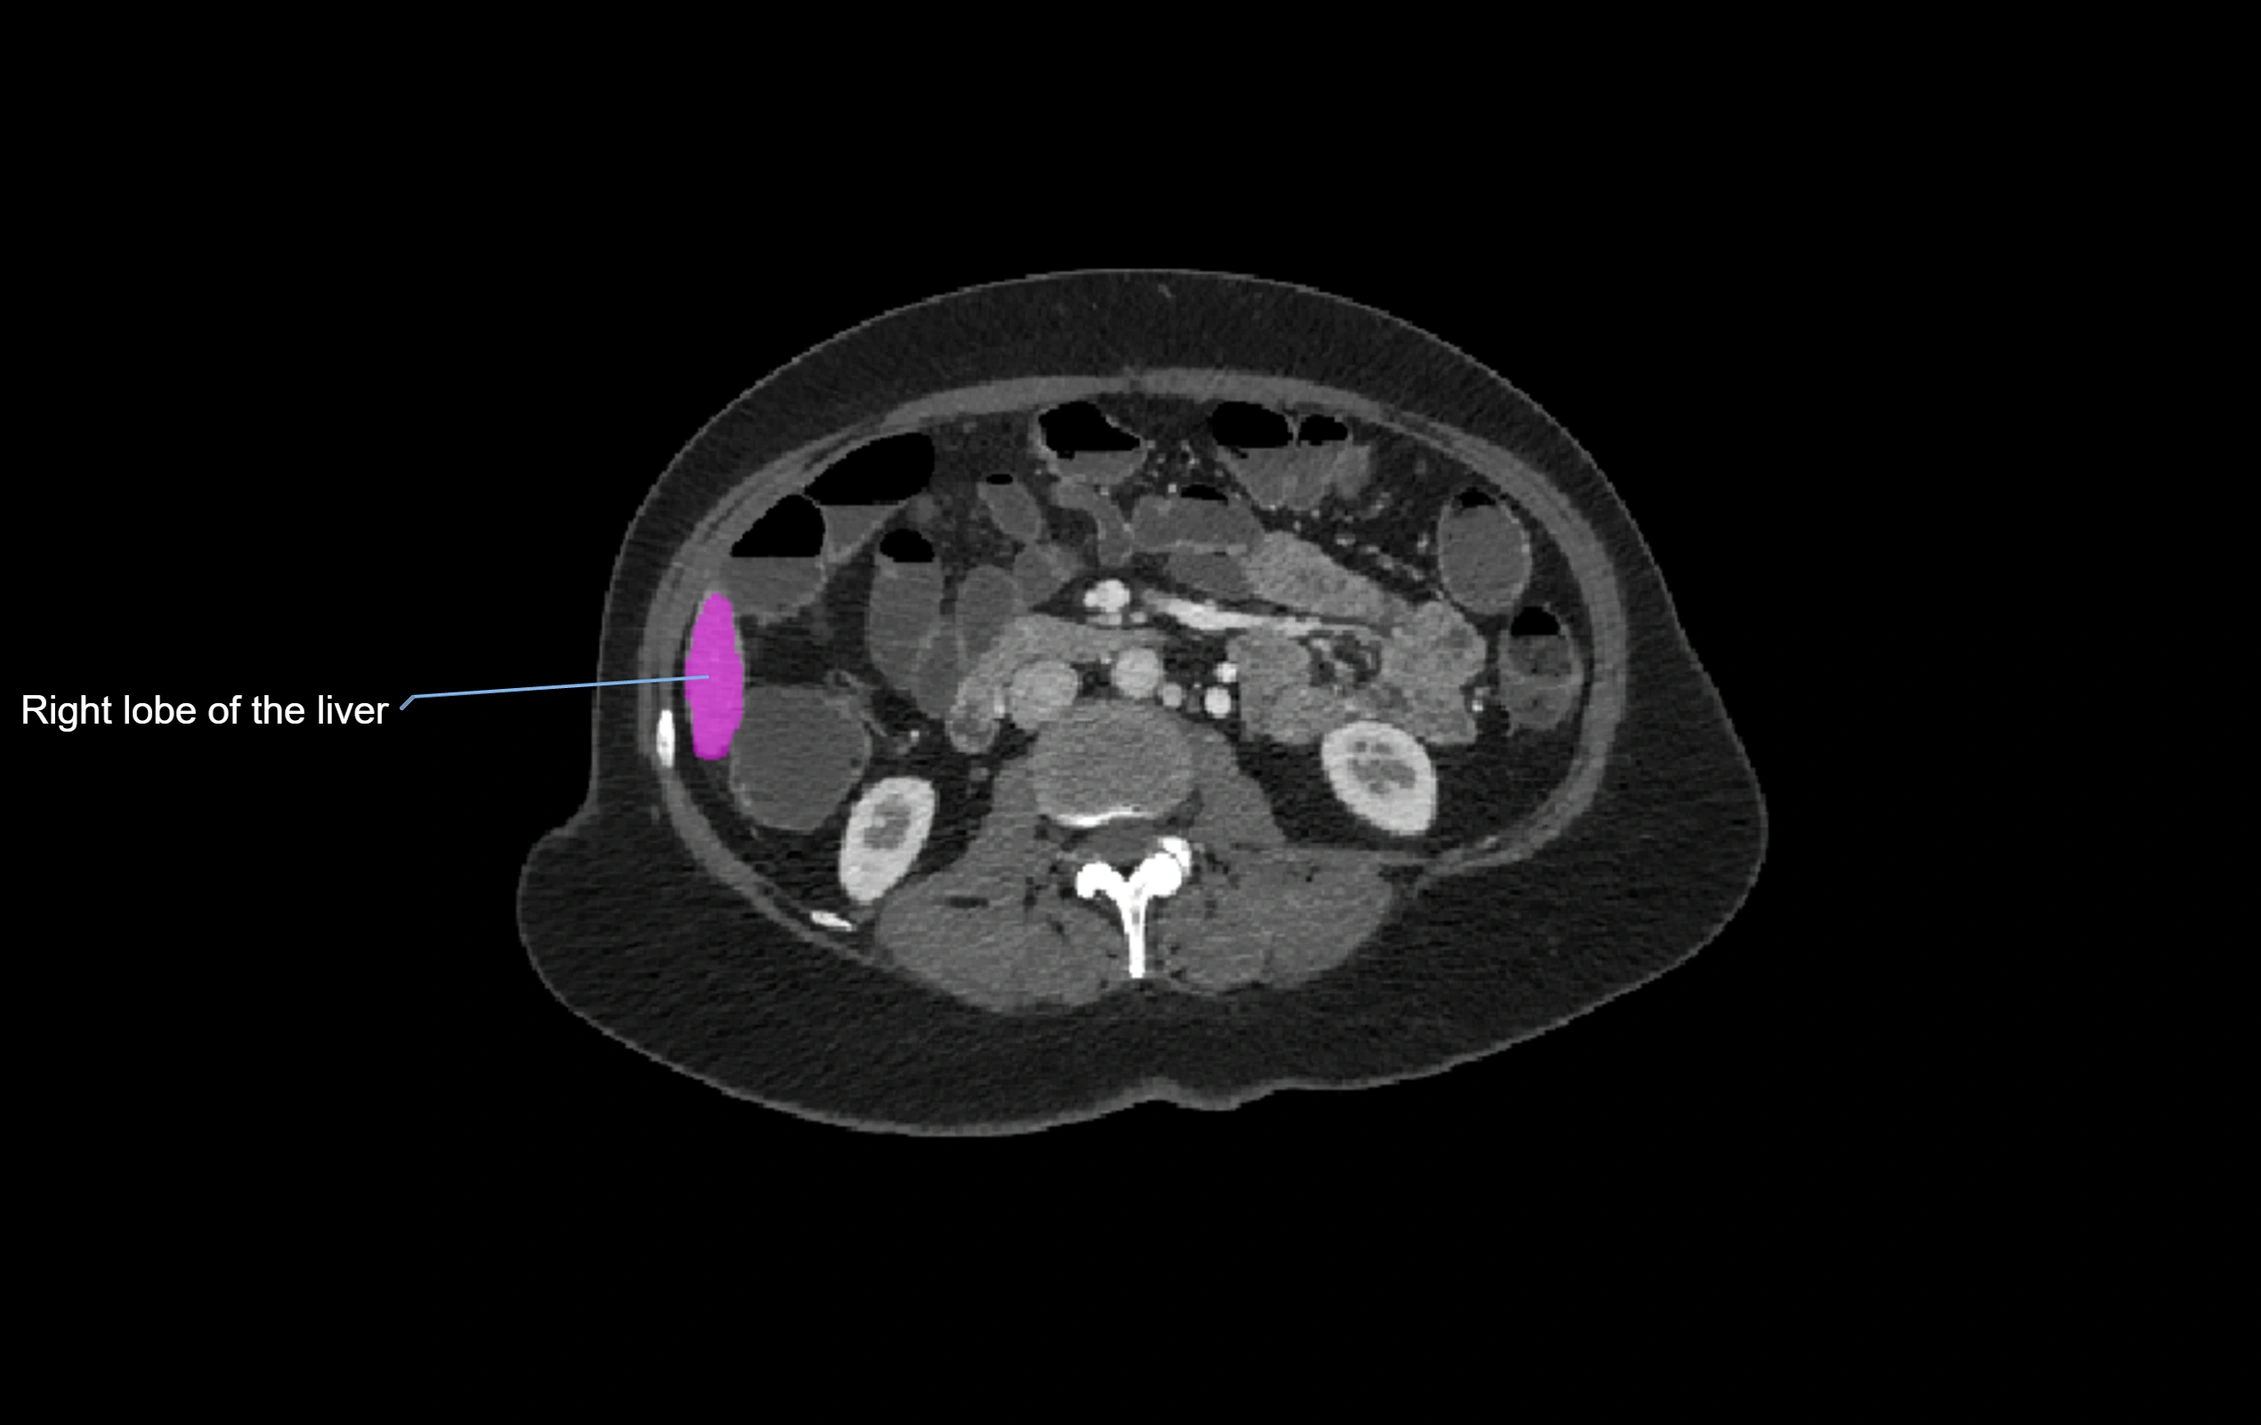

CT Image

image